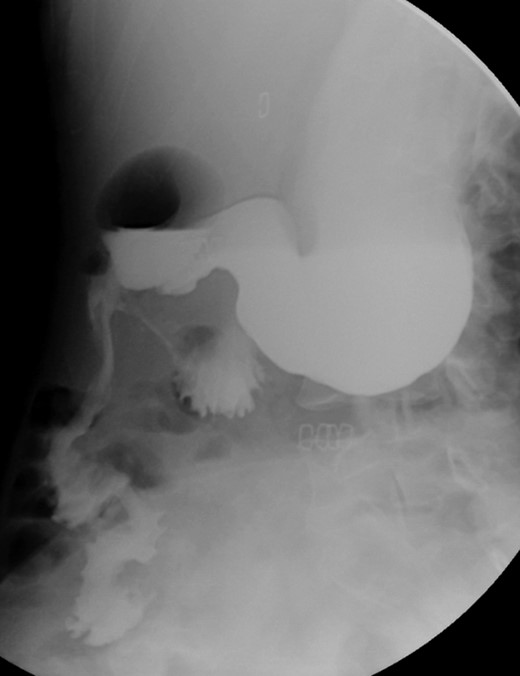

A 39-year-old Caucasian female patient presented to a General surgery outpatient clinic with complaints of epigastric pain, nausea, vomiting and weight loss for more than 5 years. The pain was worse after eating and with supine position. Vomiting was usually initiated 3–4 h after meals and consisted of undigested food. She had no significant prior medical history. On examination, the patient was extremely emaciated, with normal vital signs but with a distended abdomen and fullness over the epigastrium. She had already done an upper endoscopy that only showed gastric stasis. Abdominal ultrasound revealed a reduced angle between the AA and SMA (Fig. 1). An upper GI contrast study was requested, which revealed a distended stomach with delayed gastric emptying and lagging of contrast at the third portion of the duodenum (Fig. 2). Abdominal computed tomography (CT) scan was then performed. It demonstrated a severe distension of the stomach and proximal portions of the duodenum with constriction of the third part of the duodenum between the AA and SMA, with a reduced angle (11°) and shortened distance (4–5 mm) between these two arteries (Figs 3 and 4). These findings were suggestive of an aortomesenteric clamp. Hence, based on known findings, the diagnosis of Wilkie’s syndrome was established.

Contrasted intestinal series—distended stomach with delayed gastric emptying and reduced passage of contrast at the third portion of duodenum.